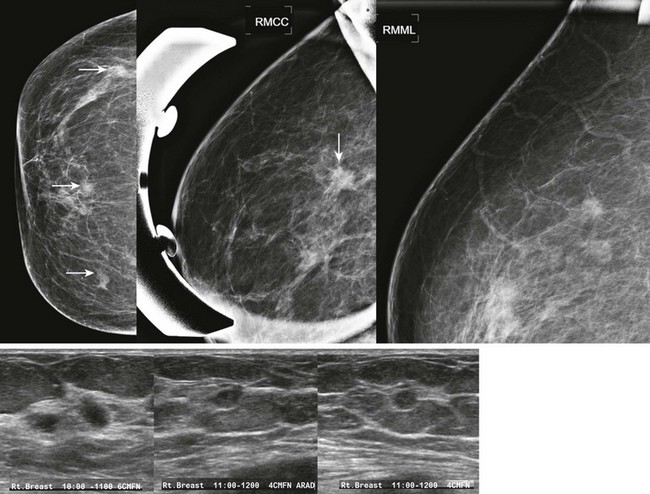

CASE 8-7. There is postsurgical deformity of the anterior right breast. Multiple masses are present in the right breast. Some of the masses (arrows) have indistinct margins. The findings are suspicious for recurrent carcinoma. Diagnostic views and US are recommended.

Magnification views confirm multiple masses, one with spiculated margins (arrow). US reveals three solid masses. Core biopsies of two masses both revealed IDC and DCIS.